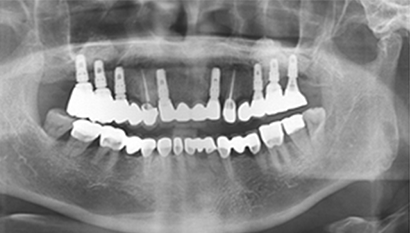

W Dental Clinic Before & After

治療前後の写真

Before

After